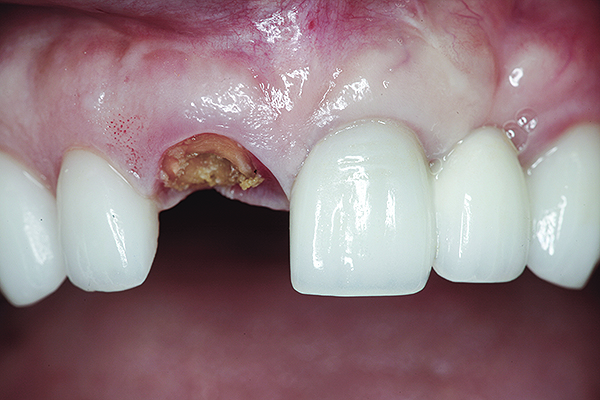

Fig 16. Try-in of the definitive titanium-nitride–coated abutment.

Figure 16

The master cast and abutment were returned to the laboratory for fabrication of the restoration (Figure 15). An all-ceramic crown (e.max®, Ivoclar Vivadent) was fabricated on the custom abutment; it matched the contours of the adjacent central incisor. After completion of custom shading, the definitive abutment and crown were returned to the restorative dentist. The abutment was tried in (Figure 16), and a radiograph was taken to confirm complete seating between the abutment/implant and the crown/abutment. The definitive abutment screw was torqued to 20 Ncm, and the screw-access opening was blocked out with Teflon tape.

The crown was inserted and secured with a luting composite (Multilink® Automix, Ivoclar Vivadent) (Figure 17); a radiograph confirmed complete removal of excess cement (Figure 18). At the 4-month follow-up appointment, the soft tissues were healed within normal limits, and the patient was pleased with the esthetic outcome of the definitive restoration (Figure 19 and Figure 20).